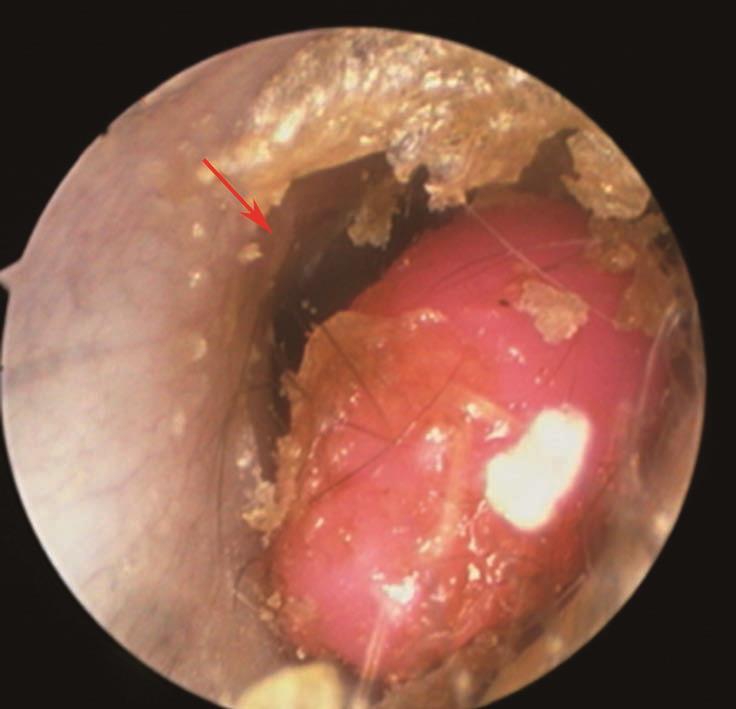

外耳道异物种类可分为动物性(如各类昆虫或爬虫类,图5-1)、植物性(谷类、豆类等,图5-2)及非生物性(如棉花、塑料、玻璃、纽扣电池、医用纱条等,图5-2)。Thompson等的一项回顾性研究揭示在162例外耳道异物中,棉花(22%)、昆虫(18%)和珠子(16%)是最常见的异物。异物可长时间滞留于外耳道,压迫周围组织,并可继发感染,最终导致局部组织炎症、坏死等,部分异物可被耵聍包绕形成耵聍栓塞。

图5-2 外耳道可见黄豆、塑料及棉花遗留